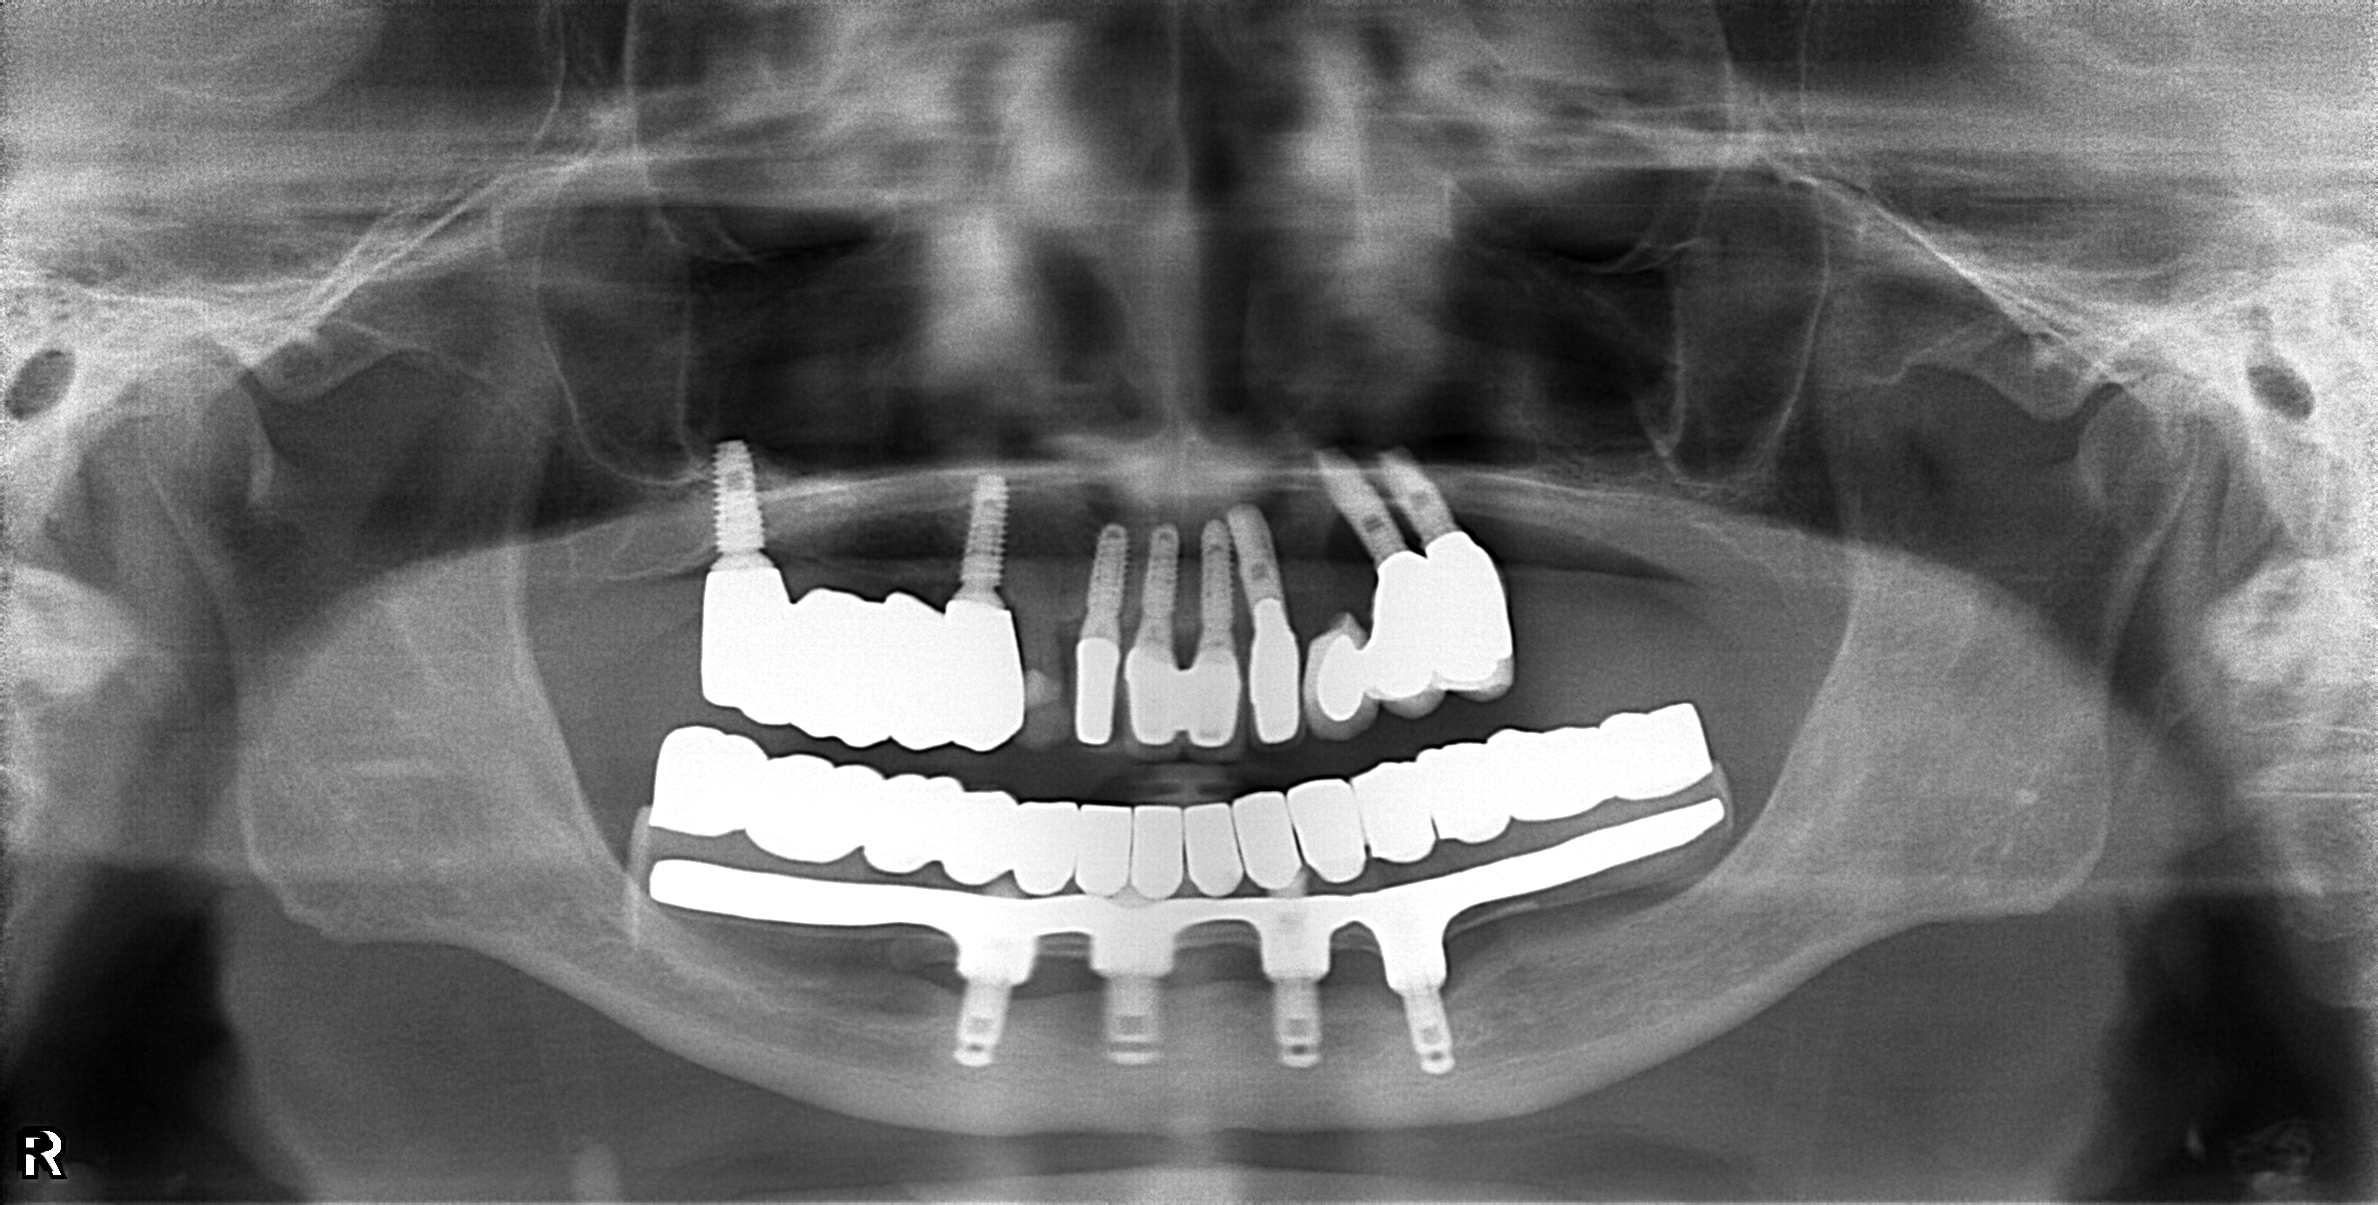

醫生透過電腦斷層及全口X光照片評估骨頭狀況決定植入的植體數量、寬度以及深度